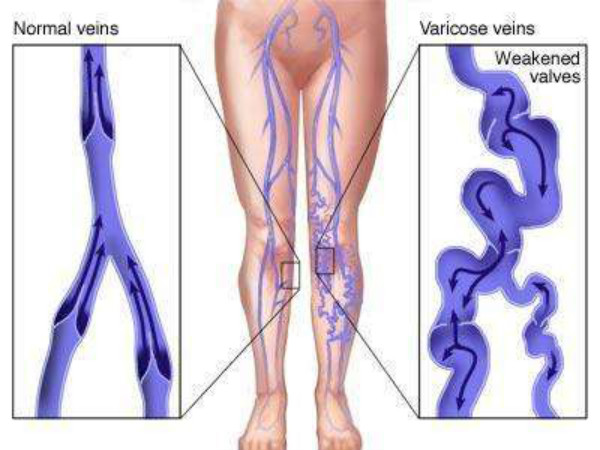

靜脈炎圖片

左小腿靜脈炎

左小腿靜脈炎症狀

左小腿血栓性靜脈炎

左腿靜脈炎

早期靜脈炎腿部

右小腿靜脈炎

右下肢靜脈炎

A:靜脈炎是靜脈的一種無菌性炎症,主要是由於血管損傷、藥物刺激、血栓等原因導致的血管通透性改變。表現為局部肢體腫脹、迴流受限、疼痛不適。個別患者可以看到沿著血管走形的紅色條索影、觸摸起來血管彈性減退,變硬。血栓性靜脈炎的患者,具體肢體出現皮膚髮……